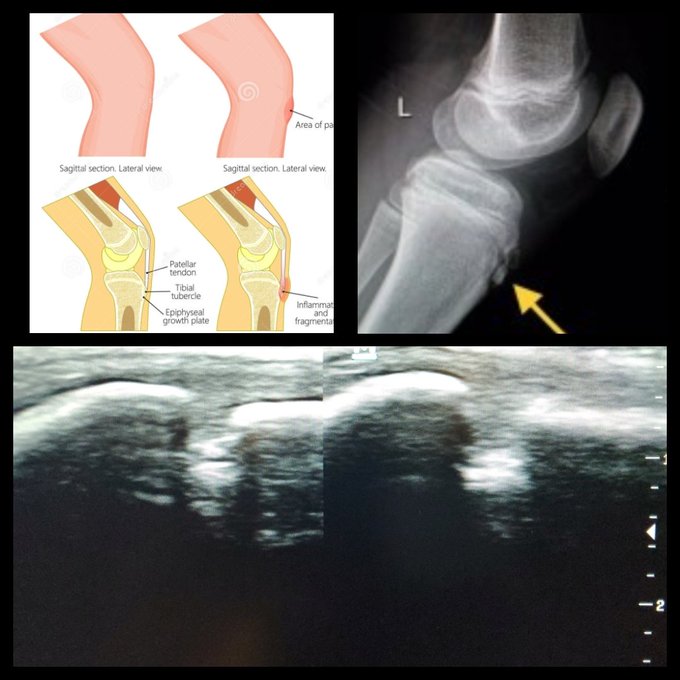

Osgood Schlatter's disease is a frequent cause of grinding anterior to rodilla in children that practice high energy activities